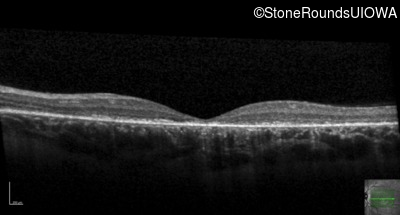

Age at visit: 15 years

OD OS

Age at visit: 16 years

Age at visit: 19 years

Age at visit: 23 years